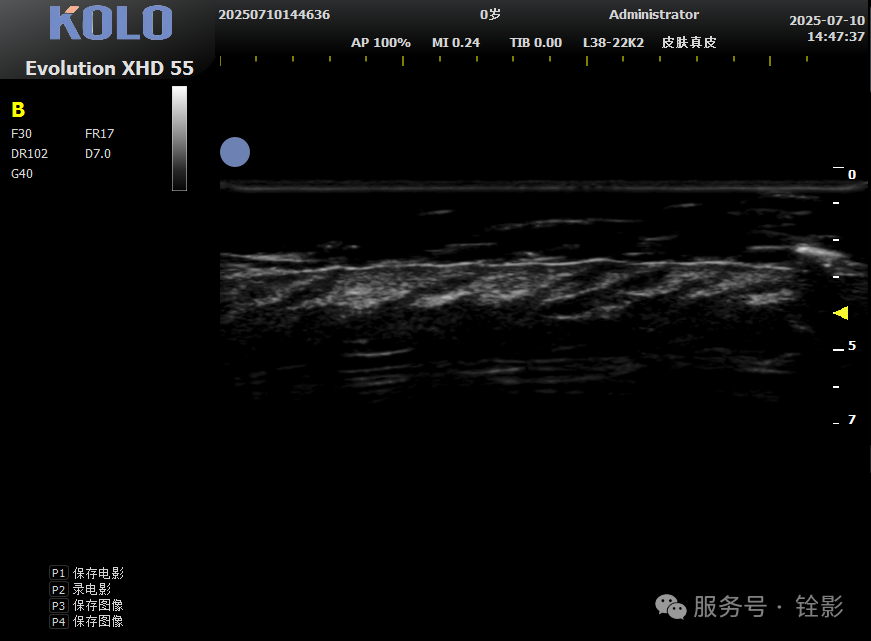

铨影高频皮肤超声:可视化高清成像,透视毛囊“生死”

铨影高频皮肤超声系统,采用全球新一代CMUT半导体超声技术和高频专用AFE数据采集芯片,实现30μm超高分辨率成像。超声搭配8-62MHz 的超高频变频探头,可清晰透视头皮皮下结构,精准分辨毛囊状态。支持B、C、PW、P四种扫描模式,无论是毛囊的形态、深度、密度,还是周围的血流情况,都能清晰呈现。

二维灰阶模式(B)

在铨影超声图像中,健康的毛囊呈现为规整的低回声结构,周围有清晰的组织边界,血流信号丰富;而萎缩或退化的毛囊则表现为结构模糊、体积缩小、回声异常,周围血流信号明显减少。这些在肉眼下完全无法察觉的差异,在超声影像中一目了然。